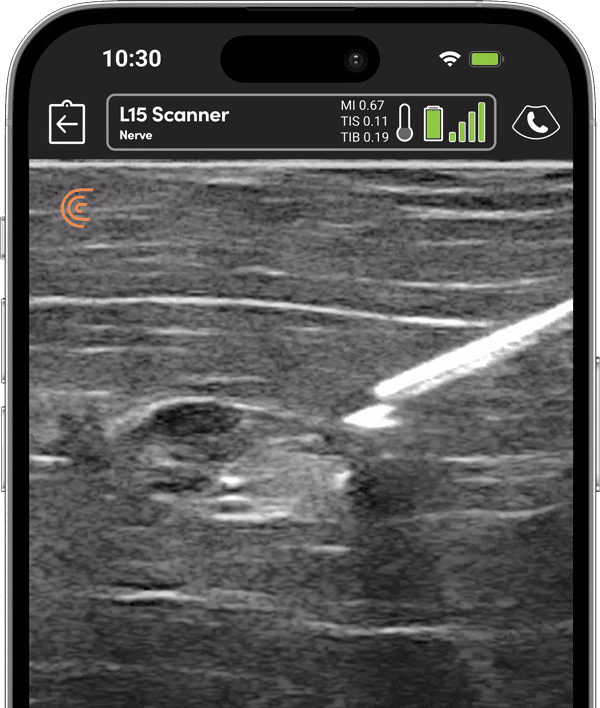

Guide Every Block with Clarity

From pre-op to PACU, guide safe, accurate blocks and pain interventions without disrupting workflow or sterility.

Visualize targets in real time for precise nerve blocks and corticosteroid injections—reducing injectate volumes and boosting safety, confidence, and patient outcomes.